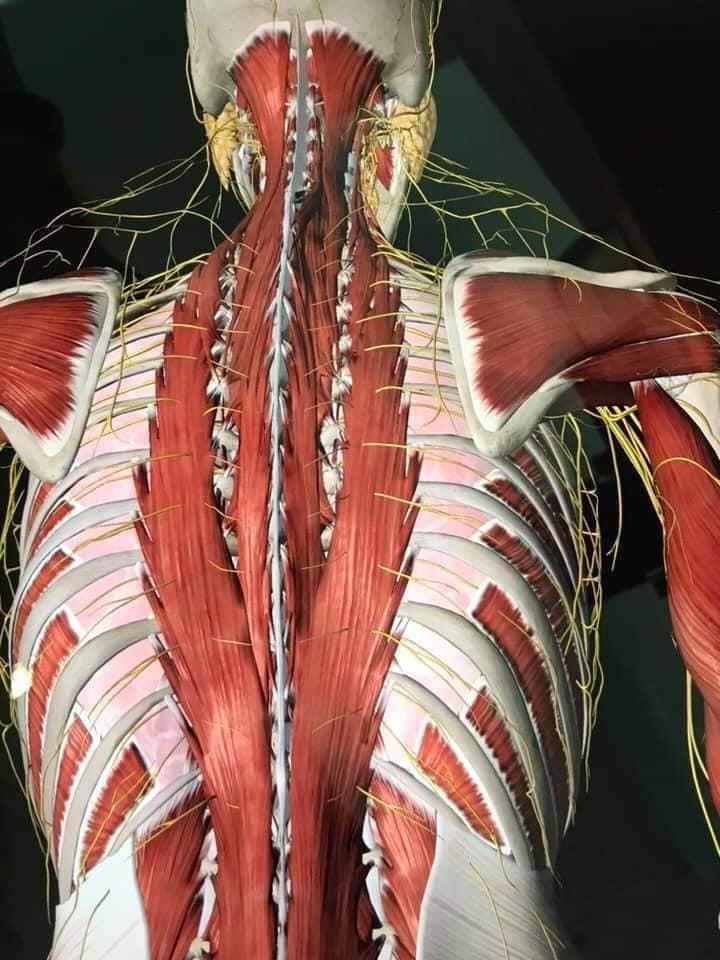

М'язова система людини є однією з основних систем організму, що відповідає за рухи, підтримання пози та стабільність. Вона складається з понад 600 м'язів, які можна класифікувати на скелетні, гладкі та серцеві м'язи. Скелетні м'язи, які є об'єктом нашого детального розгляду, дозволяють контролювати навколишній світ і виконувати різноманітні рухи. Особливу увагу в нашій статті буде приділено шейним і спинним м'язам, оскільки ці групи м'язів мають критичне значення для підтримання правильного постава та функціонування хребта.

Спинні м'язи

Спинні м'язи виконують функції підтримки хребта, а також дозволяють здійснювати рухи тулуба.

Глибинні спинні м'язи

М'язи, що забезпечують стабільність хребта: М'язи, що розташовані між хребцями: включають мускулатуру, яка забезпечує стабільність і підтримку хребта, а також дозволяє здійснювати рухи хребта.

М'язи, що здійснюють ротацію та нахили

М'язи, що забезпечують ротацію хребта: Ротаційні м'язи: допомагають у здійсненні обертальних рухів тулуба, а також у підтримці рівноваги і стабільності хребта.